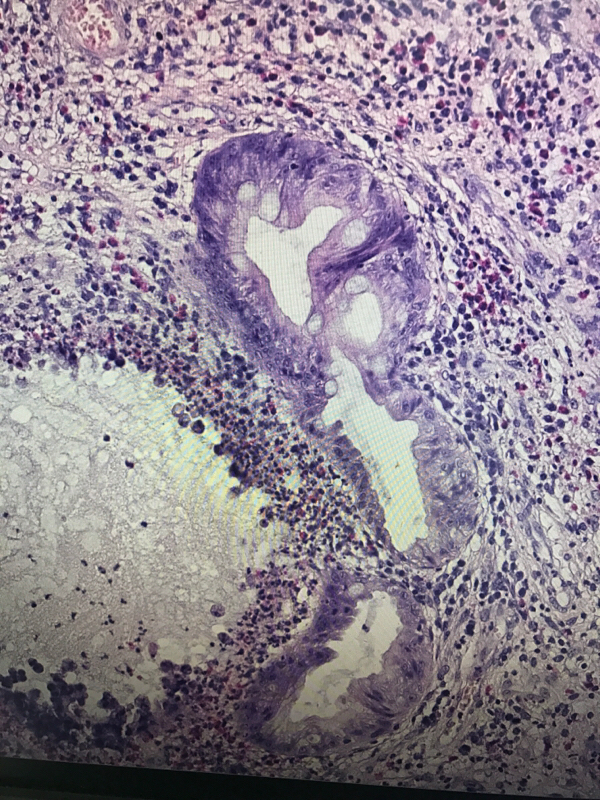

直肠息肉

性别

男

年龄

19

临床诊断

一般病史

血便4天

标本名称

大体所见

灰红结节一枚,大小1✖️0.6✖️0.6cm,切面灰红,质软

管状腺瘤,低级别还是高级别?

幼年性息肉,灶性低级别

考虑有高级别

幼年性息肉?

幼年性息肉